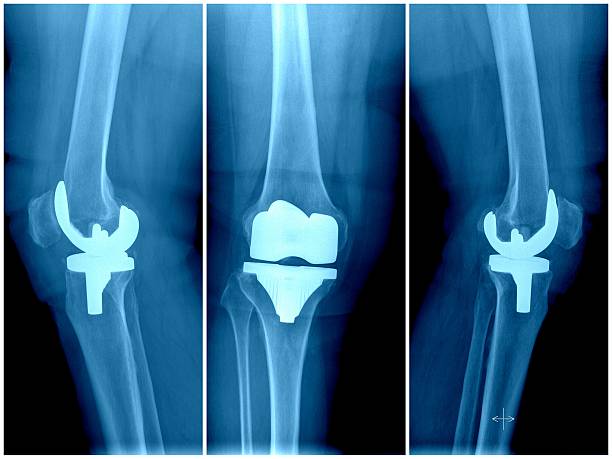

The Orthopedic Reconstruction Market includes a wide range of surgical procedures and medical devices designed to restore joint function, mobility, and structural integrity of bones. These procedures are primarily used in hip replacement, knee replacement, shoulder reconstruction, and trauma-related surgeries.

Orthopedic reconstruction solutions involve the use of prosthetic implants, fixation devices, and biomaterials to repair or replace damaged joints and bones. These treatments are essential for patients suffering from osteoarthritis, rheumatoid arthritis, fractures, and degenerative bone diseases.

Knee Replacement